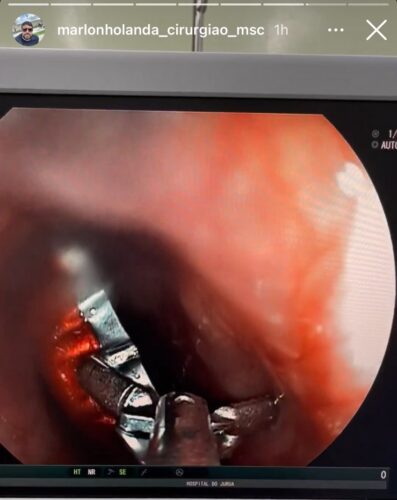

Um homem, de 35 anos, deu entrada no Hospital do Juruá por volta das 16hrs da tarde do último domingo (01), após engolir uma tampa de garrafa em Ipixuna (AM). O paciente foi encaminhado para Cruzeiro do Sul para fazer uma endoscopia e a retirada da tampa. O procedimento foi feito aproximadamente 21h do mesmo dia.

“Sempre está acontecendo isso, dos pacientes engolirem ossos de galinha, objetos pontiagudos, espinha de peixe e vir até o Hospital do Juruá para receber esse tipo de serviço. Até pouco tempo esses pacientes precisavam ir para Rio Branco, agora já fazemos aqui atendendo todo o Vale do Juruá e algumas cidades do Amazonas”, explicou o médico Marlon Holanda.